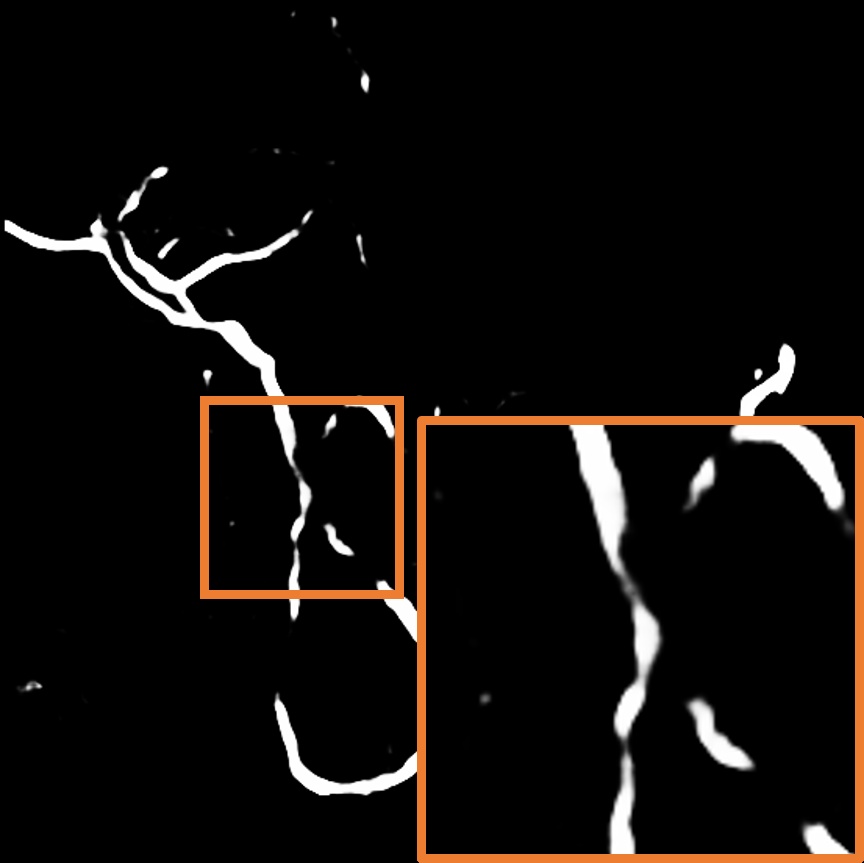

Layer separation bootstrapping.

To validate the effectiveness of the layer separation bootstrapping, we train foreground and background canonical images using the same representation. The results are shown in Table 2, where optimizing both foreground and background canonical images simultaneously leads to a decrease in the Dice score by 0.0055. The comparison is shown in Figure 8 (a), where the orange area indicates the difference between without and with Layer separation bootstrapping. The bottom-right corner shows a zoom-in patch, highlighting the significant effect of the bootstrapping step.